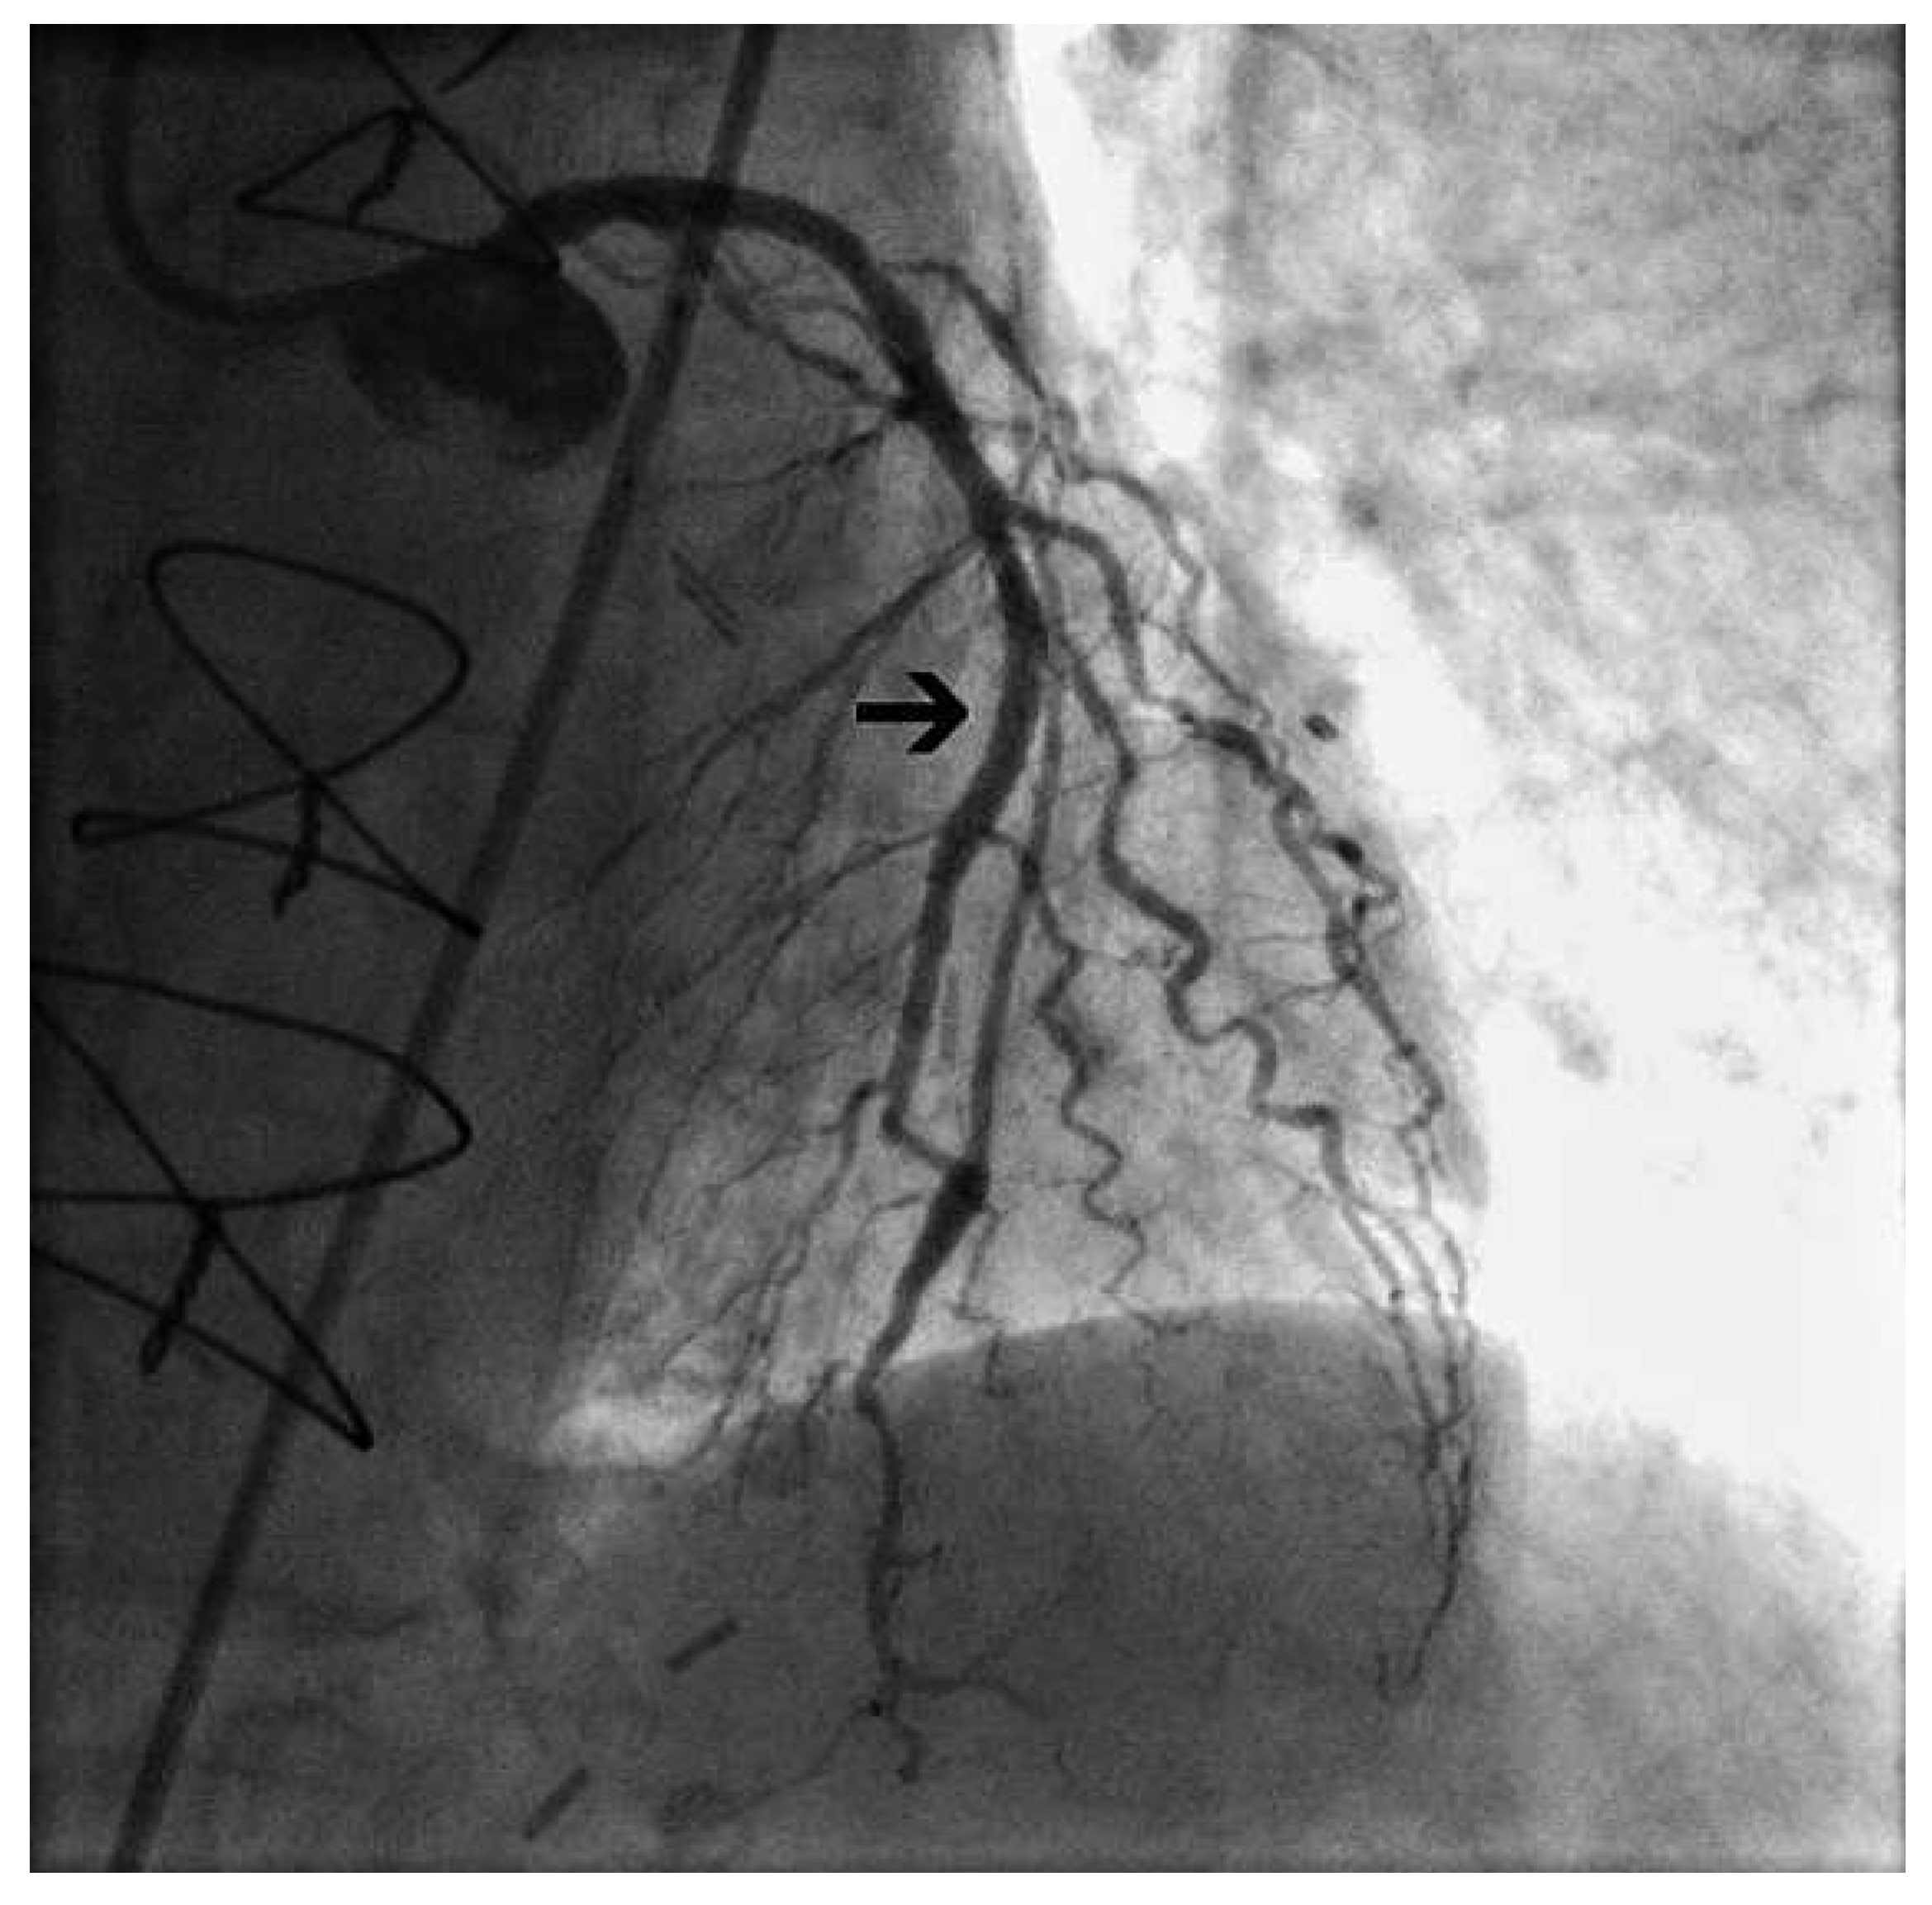

In lack of evidence about the best treatment strategy in this situation, we proceeded to revascularization of the proximal LAD by percutaneous coronary intervention (PCI) and stent implantation, which limited retrograde flow in the graft; a diastolic steal phenomenon was no longer observed (Figure 3 and Figure 4). Nine months later, the patient had not experienced any further anginal symptoms, neither at rest nor during haemodialysis.

Figure 4. After stent implantation (black arrow), retrograde flow of contrast medium in ventricular systole is limited.